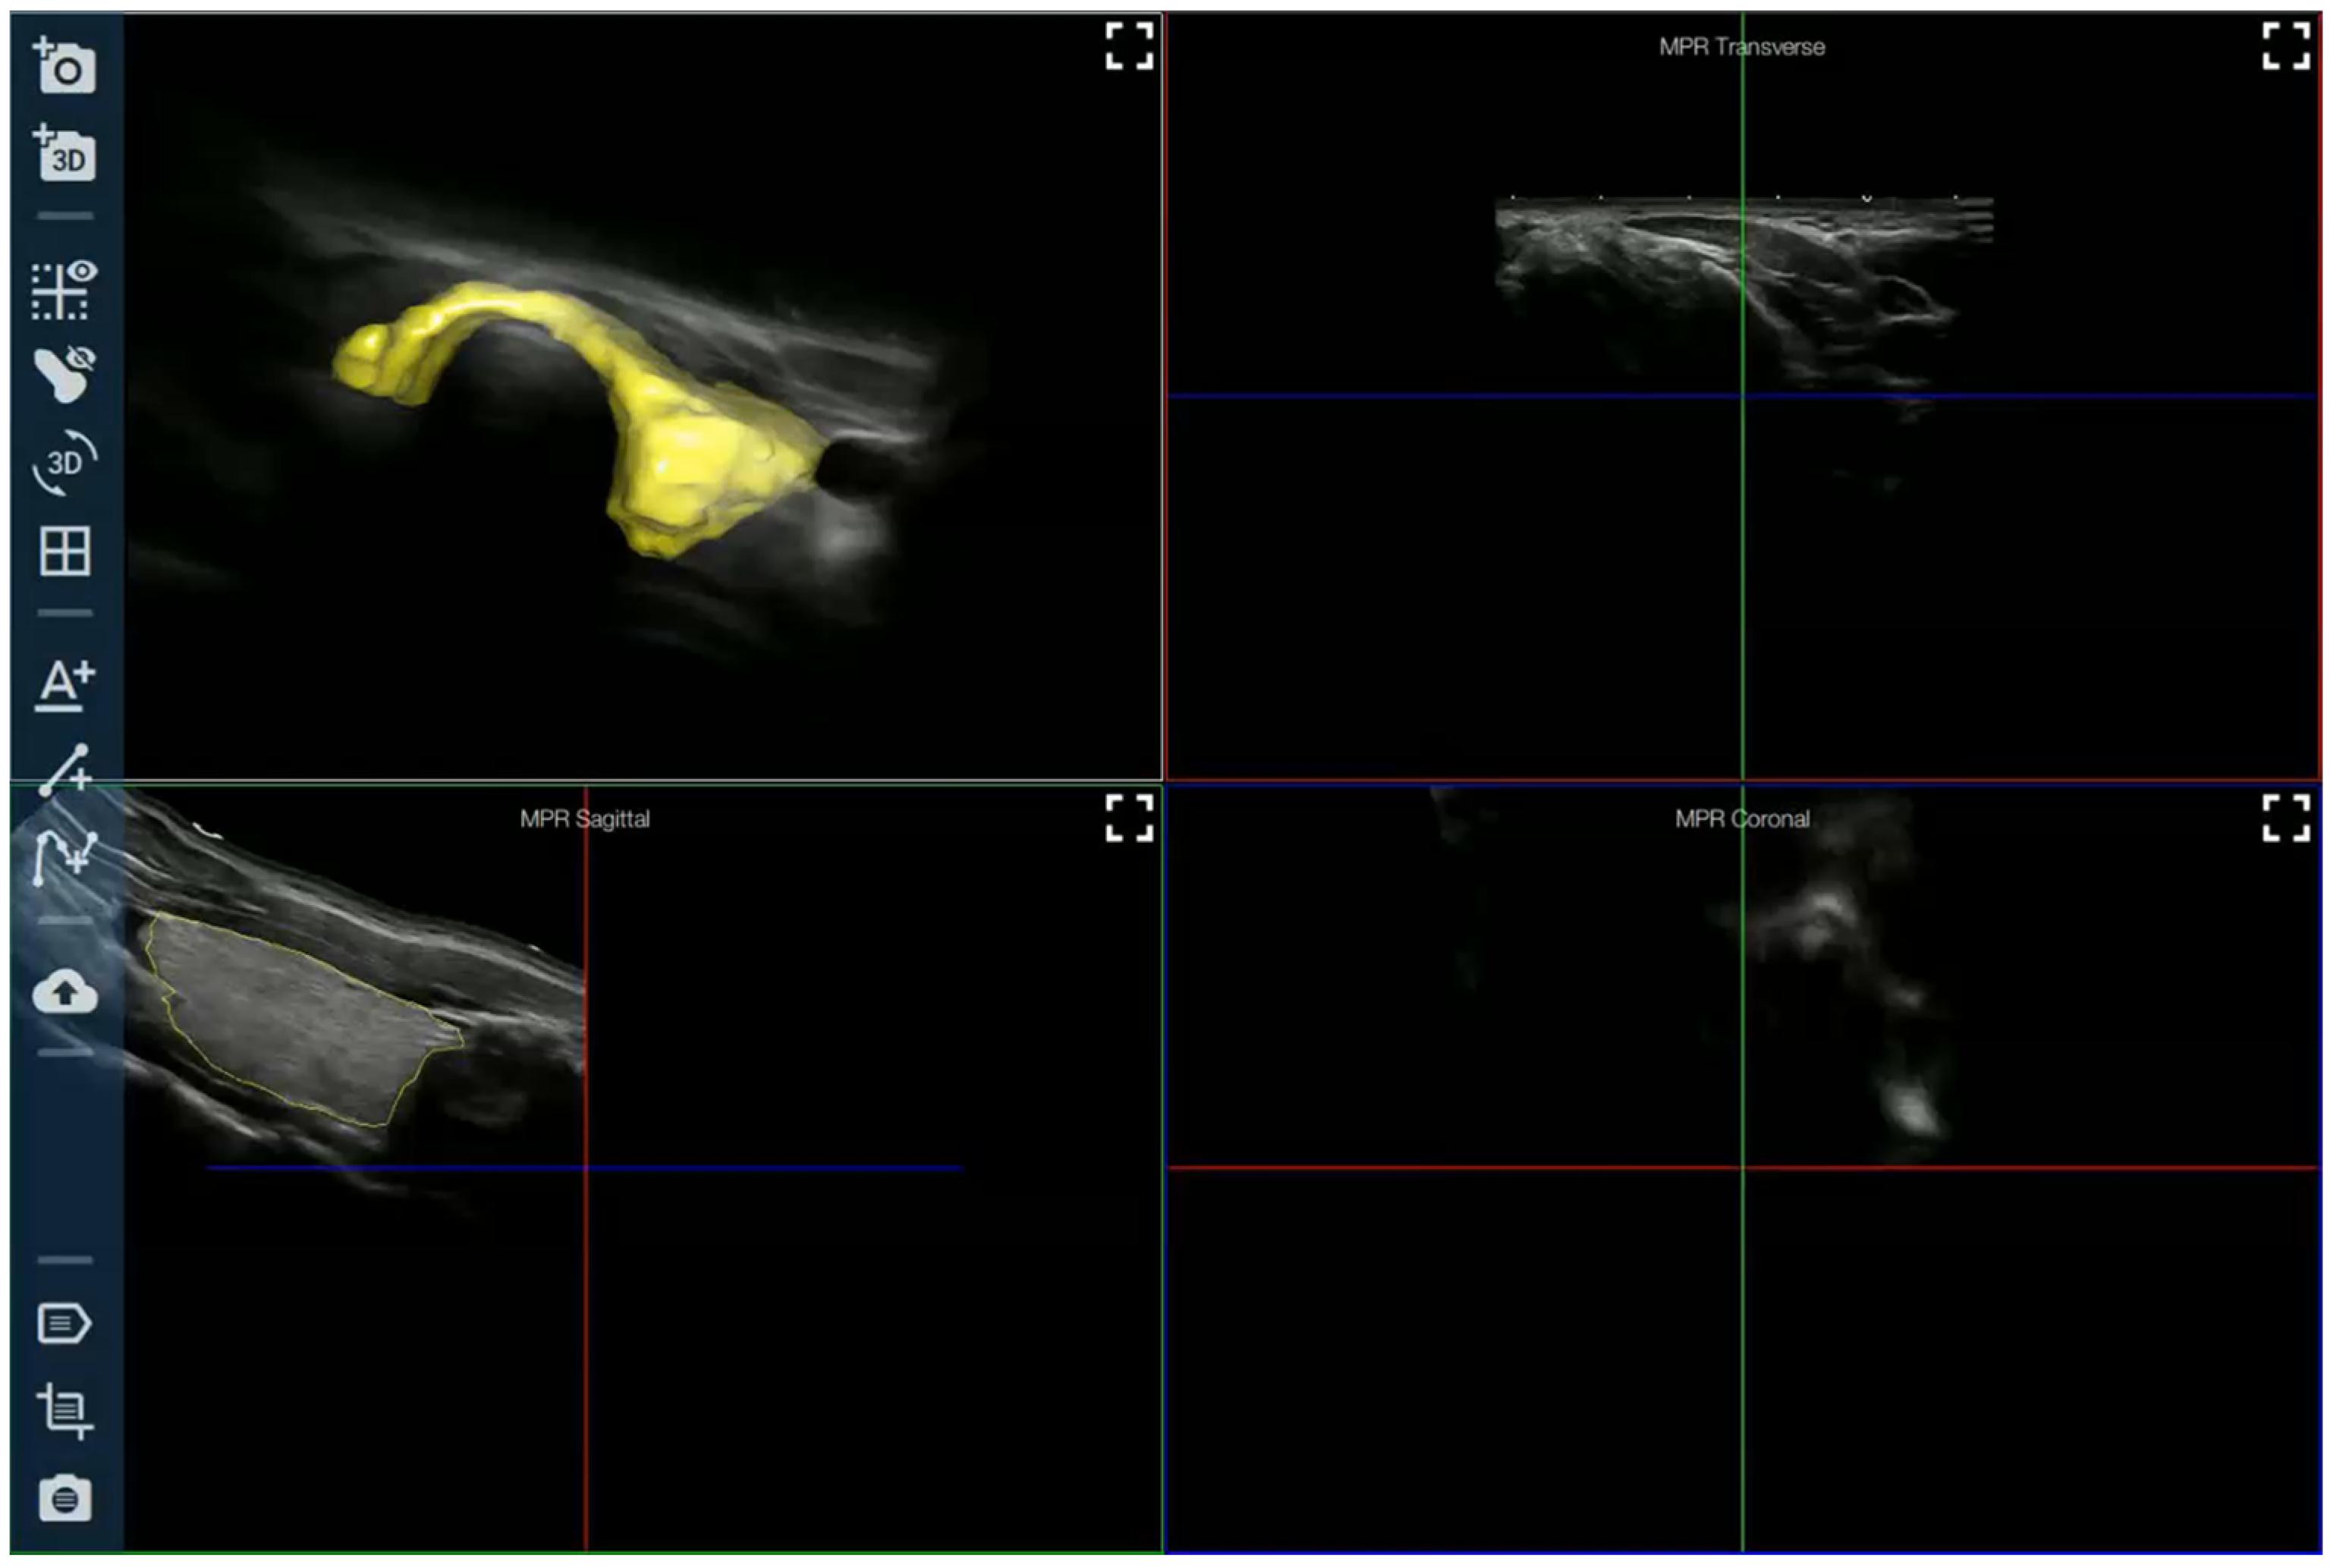

AI Applied to Ultrasound Imaging

- Improvement in diagnostic efficiency: artificial intelligence algorithms have been successfully tested in the evaluation of ultrasound images of thyroid nodules, the classification of lesions, and the prediction of malignancy, showing the ability to improve diagnostic efficiency and reduce evaluation time.